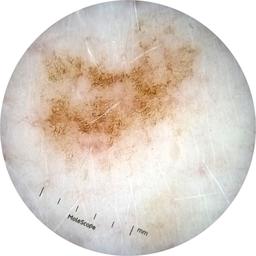

ISIC_3754278

MEL-SELF Trial, https://www.sydney.edu.au/medicine-health/our-research/research-centres/melself-project.html

Clinical

Field Value

acquisition_day 135

age_approx 65

anatom_site_1 Upper extremity

anatom_site_general upper extremity

diagnosis_1 Benign

diagnosis_confirm_type single image expert consensus

image_type dermoscopic